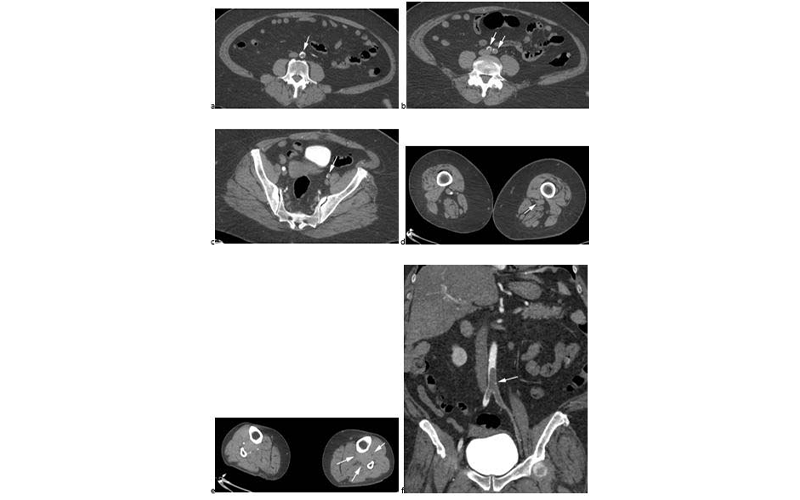

Goldman Revised Fig. 2 Feature

CTA images from a 63-year-old woman with COVID-19. Images through the (a) distal abdominal aorta, (b) proximal common iliac arteries, (c) external iliac arteries, (d) popliteal arteries, and (e) anterior tibial, posterior tibial, and peroneal arteries demonstrate lack of contrast opacification on the left (arrows). Hyperdensity along the periphery of the vessels in a and b corresponds to contrast rather than calcium. Note that the arrows in e point to the expected location of the vessels. (f) Oblique coronal reformatted CT image demonstrates clot at the aortic bifurcation (arrow).